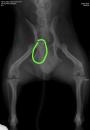

El veterinario es quien deberá valorar el alcance de la lesión. Debe tratarse de un veterinario con conocimientos actualizados de traumatología, ya que es importante realizar un buen diagnóstico, así como implantar un tratamiento adecuado. Hay que descartar la presencia de fracturas asociadas. La prueba escogida acostumbra a ser la radiografía. No es extraño que deba sedarse al perro, primero para evitarle el dolor que le supondría la manipulación, necesaria para el correcto diagnóstico, y, segundo, para conseguir la inmovilidad que se precisa para posicionar al perro de forma que las radiografías estén bien hechas, lo que es básico para tener seguridad en el diagnóstico. Además, para devolver a su posición los huexos luxados, es necesario anestesiar al animal.